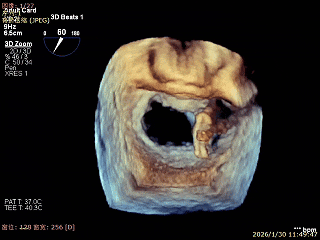

3D Enface 2区及3区前叶脱向左房

3D Enface 可见反流由2区3区从前后冲出

3D Enface下组织桥稳定残余外侧前叶脱垂

3D Enface上彩可见夹子内侧无反流,残余外侧反流

3D Enface下组织桥稳定无反流

夹子释放后,反流基本消失

LVOT切面可见主瓣二尖瓣术后反流基本消失